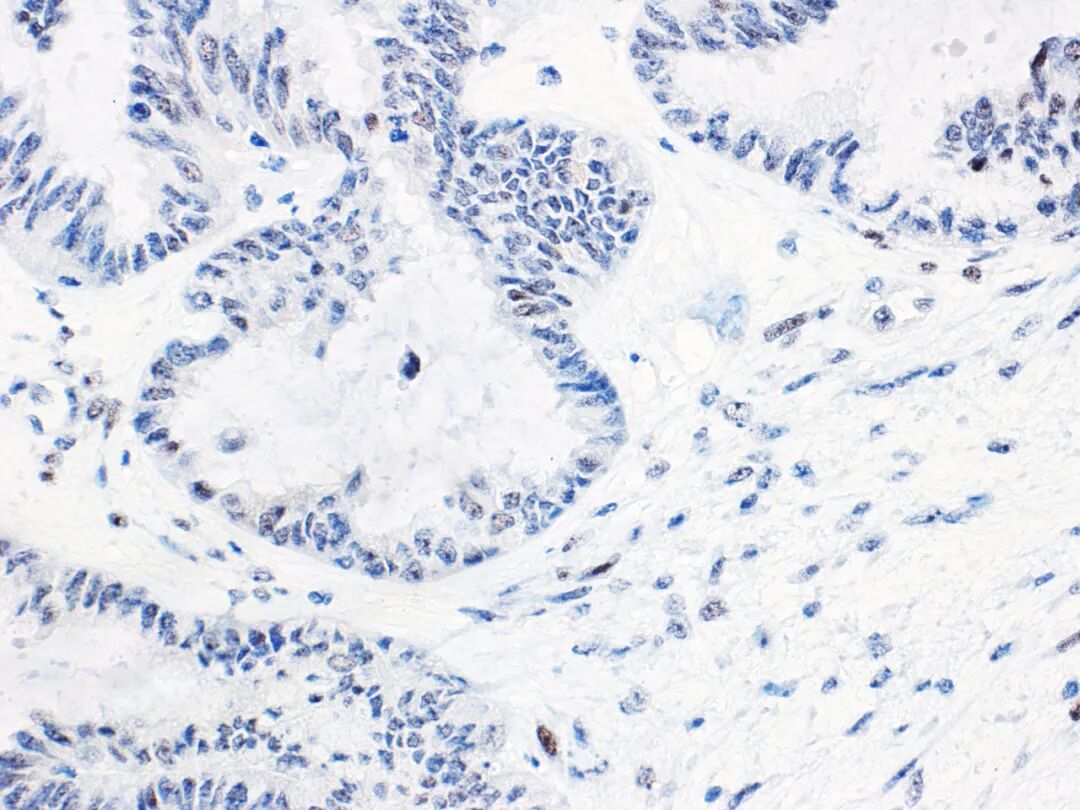

低级别浆液性癌的免疫组化p53多表达为野生型。但有少数病例具有取得性Tp53基因突变的报道,这类病例极为罕见,因此出现p53的异常着色模式通常不诊断卵巢低级别浆液性癌。这点在小的活检病例诊断中尤其重要,因为有些高级别浆液性癌由于呈微乳头状结构、细胞核为中等程度异型性,可能会类似低级别浆液性癌。需要注意的是有约2%的输卵管、卵巢高级别浆液性癌会有Tp53基因突变而其终止密码子超出了正常时候的位置,导致产生无功能的p53蛋白。因此,即使免疫组化p53表达正常的浆液性肿瘤也可能会是卵巢高级别浆液性癌,所以还是要结合形态学并建议加做必要的分子检测。有多家组织研究证实p53异常表达与卵巢子宫内膜样癌生存时间缩短有关。在I/IIA期卵巢子宫内膜样癌患者中也有类似结果。分期较低的卵巢子宫内膜样癌中,p53异常表达是可靠、强有力的生存预后指标。免疫组化p53结果预测卵巢黏液性肿瘤(如图3所示)中Tp53基因突变情况的准确性也比较高。表明Tp53基因突变与卵巢黏液性交界性肿瘤演进相关。顺利获得免疫组化方法来对大量卵巢黏液性肿瘤中p53的情况进行评估,未发现其结果与预后有关。然而,少量黏液性交界性肿瘤中的免疫组化p53结果与死亡风险增加有关。尽管对于这类患者的治疗方面方案有限,但免疫组化p53正常表达提示临床表现不同寻常的黏液性交界性肿瘤(如肿瘤破裂者)出现进展的风险较低。

图3.卵巢浆黏液样癌-野生型p53正常表达